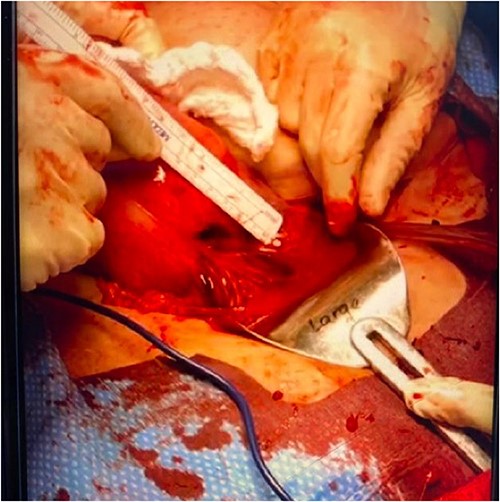

Upon abdominal entry, hemoperitoneum was identified and 200 mL of blood was evacuated. Both fetuses were noted to be free-floating in the abdomen (Fig. 2). A 2-cm uterine rupture was identified likely along the prior hysterotomy site (Fig. 3). An ~3 × 3 cm non-expanding hematoma was noted just under the serosa in the midline of the lower uterine body. The placental tissue and clots within the uterus were removed with sharp curettage through the 2-cm uterine rupture site. The hysterotomy was then closed with 2-0 Vicryl in a running-locked fashion. The fascia, subcutaneous tissues, and skin were closed in standard fashion.

Two-centimeter complete uterine rupture site on the anterior lower uterine segment, likely at the site of prior hysterotomy.